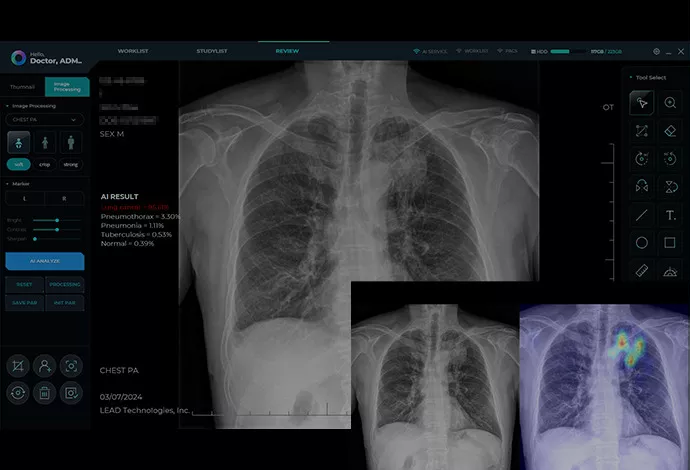

AI-Driven Accuracy and Uncompromising Safety

The device is equipped with built-in AI image enhancement software, providing clinicians with unprecedented clarity. Simultaneously, safety remains a core priority in the system’s development. The Nooka includes a safe-distance sensor and specialized filters for pregnancy and pediatric care. Finally, the device is FDA-approved and has undergone rigorous safety testing for three years, ensuring it meets the highest international medical standards.

- Superior Imaging: Works with DR panels and laptops, enhanced by built-in AI for sharper, diagnostic-grade images.

- Intuitive Interface: User-friendly software designed specifically for medical professionals

- Patient Management: Comprehensive patient data organization and retrieval

- Image Enhancement: Advanced post-processing tools for optimal diagnostic clarity

Software System

- Operating System: Windows 10/11 Professional 64 bit

- DICOM Compatibility: Full DICOM 3.0 compliance

- Image Formats: DICOM, JPEG, TIFF, BMP

- Database: Integrated patient database with backup capabilities

- Network Connectivity: Ethernet, Wi-Fi, USB connectivity